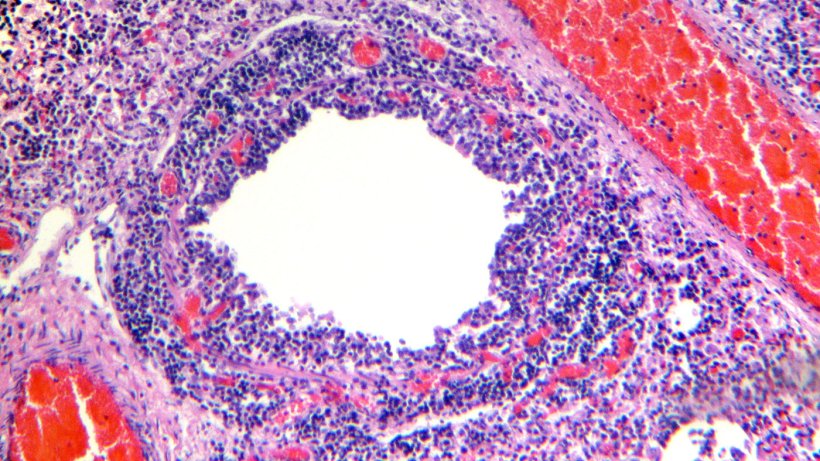

Examen histológico del tejido pulmonar mostrando infiltración linfocítica de la lamina propia y la submucosa de los bronquios (figuras 4 y 5).

Figura 5. Infiltrado linfocitario perivascular.